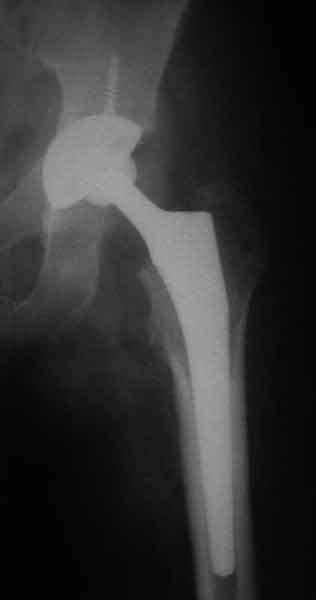

Коллеги, обещанный follow-up.

Больного прооперировали на прошлой неделе (цементный протез, цемент с гентамицином). Использовали задне-боковой доступ. В области перелома подвижности практически не было, так что тему сообщения уместно заменить на "неправильно сросшаяся шейка". И в головке, и во впадине

были значительные дегенеративные изменения, так что ни биполяр, ни остеосинтез тут неуместны (хотя это предлагали в ortopod'е). После релиза удлинили ногу на 3 см. Дальше удлинять побоялись из-за

натяжения седалищного нерва, хотя в принципе можно было бы еще 15-20 мм нарастить. По послеоперационной рентгенограмме анатомическое укорочение порядка 15 мм. Клинически при ходьбе - 4 см, но это за счет перекоса таза.

The patient underwent cemented THR on last week. Postero-lateral approach was used. There was only minimal motion at the fracture site and we had to cut the femoral head with oscillating saw. The femoral head was deformed with it's cartilage completely absent in some areas.

Acetabulum showed gross degenerative changes, especially in superior rim. So I think it was right choice not to do ORIF in this case. After some soft tissue release we've lengthened the leg up to 3 cm. Further lengthening was possible but we stopped at that moment due to tension of n. ischiadicus. Now patient walks with crutches. Leg length discrepancy is about 4 cm due to pelvic tilt (discrepancy on post-op x-ray is 15 mm).